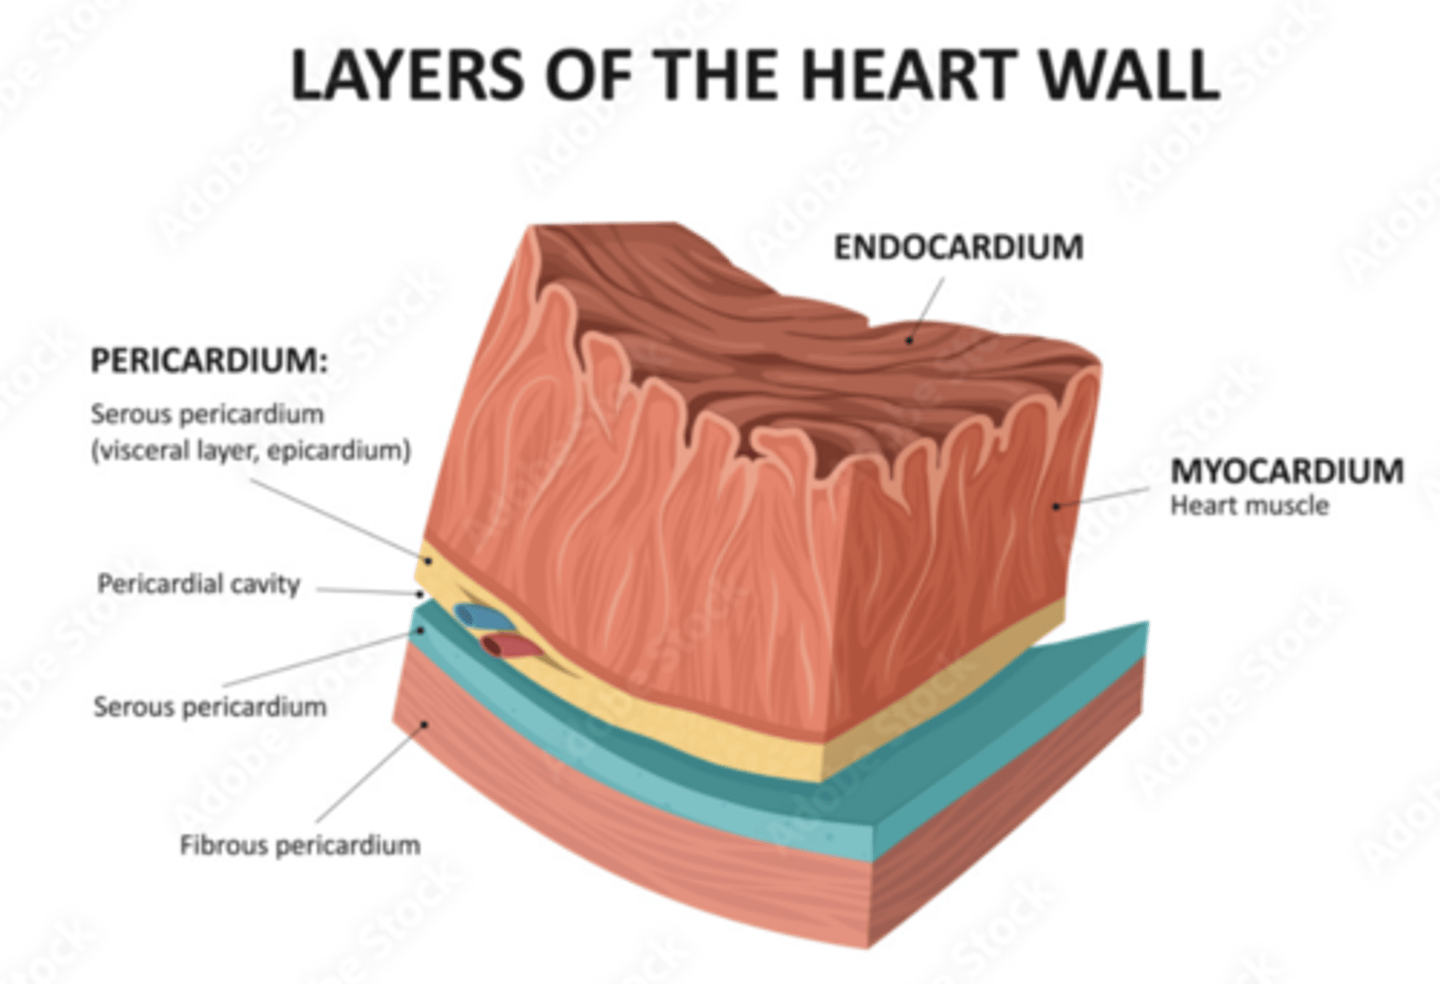

What are the layers of the pericardium?

The pericardium consists of two main layers:

- the fibrous pericardium

- the serous pericardium

How is divided the serous pericardium?

. Visceral layer or Epicardium (innermost). Adheres to the heart

. Parietal layer (outermost)

Between these layers is the pericardial fluid (pericardium cavity )

What is the fibrous pericardium?

the tough, outer layer

protects the heart

maintains its position in the thorax.

defines the boundaries of the medium mediastinum

What are the layers of the heart?

Epicardium: outermost covering.

Myocardium (right << left)

Endocardium or endothelium: inner thin layer of simple squamous epithelium